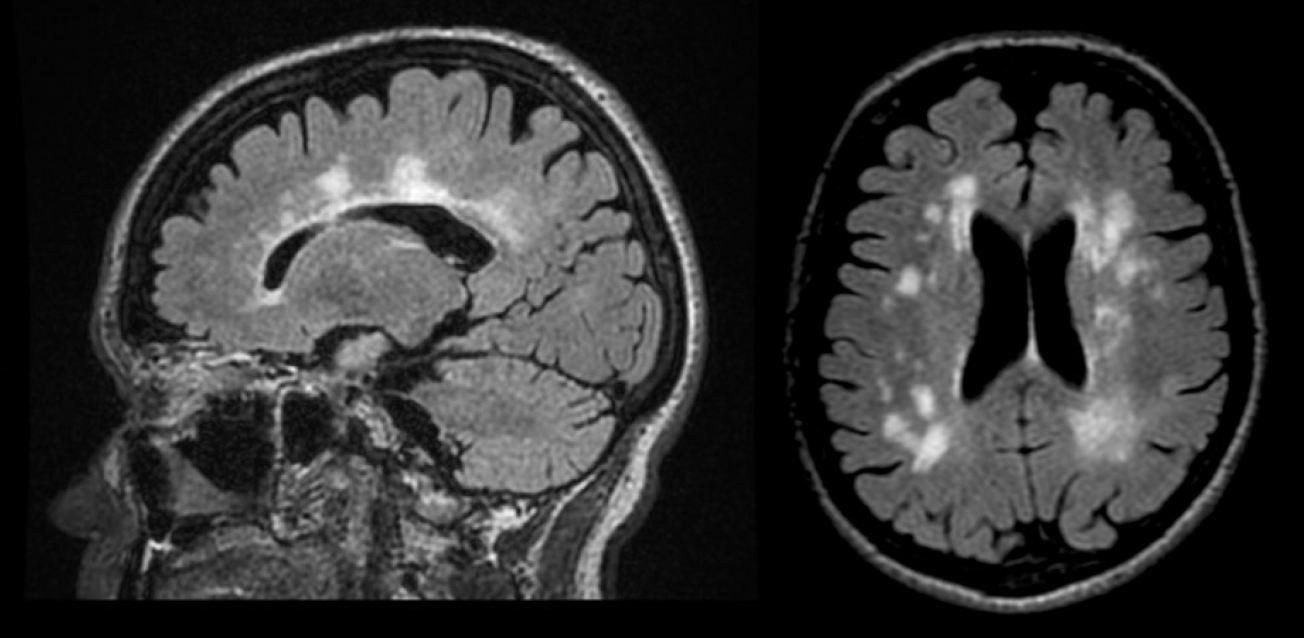

Results: A 73-year-old woman was referred to the movement disorder clinic for progressive walking difficulty with stiffness in her right leg. She had been initially investigated at age 46 by a general neurologist. A brain MRI had reveled bilateral frontoparietal and periventricular white matter lesions compatible with MS, and a repeat MRI showed progression of her white mater lesions. The patient was diagnosed with primary progressive MS.

Conclusion: To the best of our knowledge, this is the first case of DYT5 masquerading as MS. MS-like white matter changes on the MRI can be a misleading feature, complicating the diagnosis. Early recognition of DRD, especially in families with a history of neurological symptoms, is essential for initiating effective treatment with levodopa and preventing unnecessary interventions. This series demonstrates how DRD can mimic MS, emphasizing the need for heightened clinical awareness and the role of genetic testing in making an accurate diagnosis.

Figure 2 – MRI